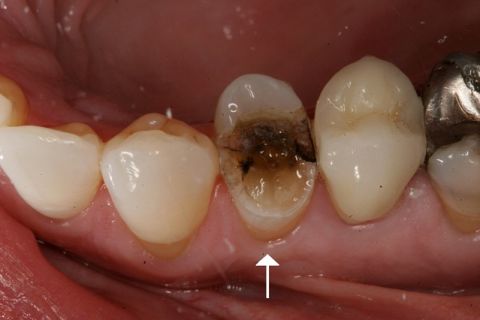

TRÁM RĂNG

Trám răng là thủ thuật được thực hiện khi bạn bị sâu răng. Sâu răng là tổn thương tạm thời xuất hiện trên bề mặt của răng.